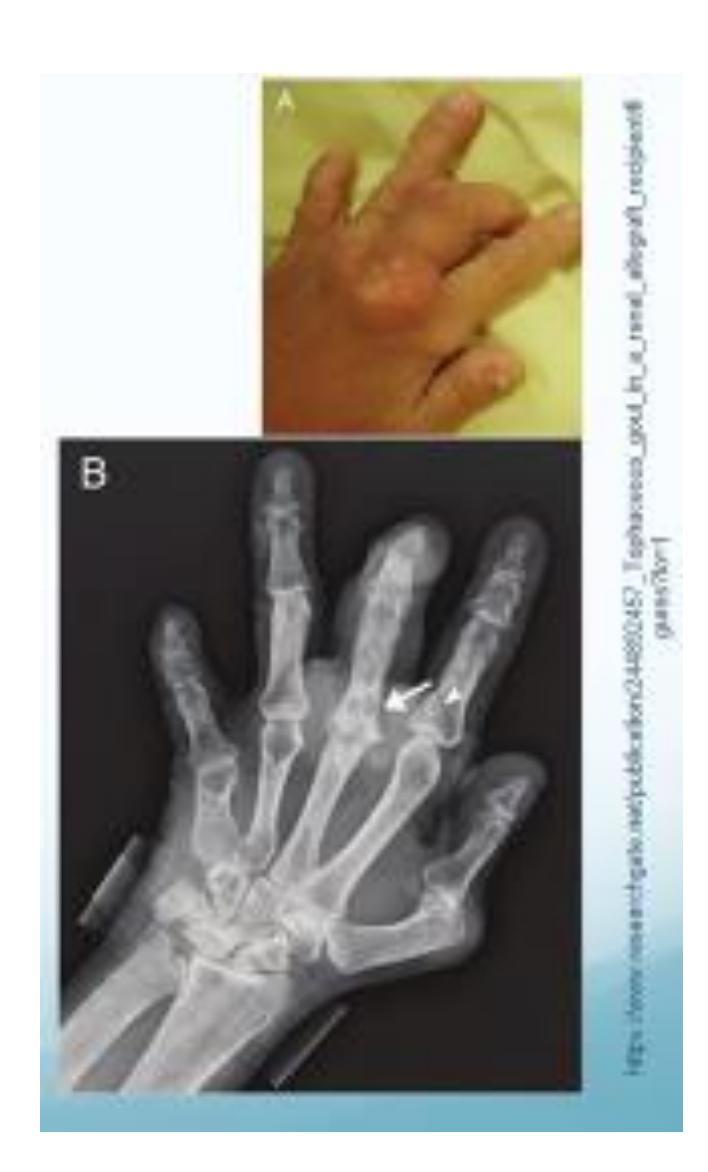

Gout

- Tophus formation visible on radiograph